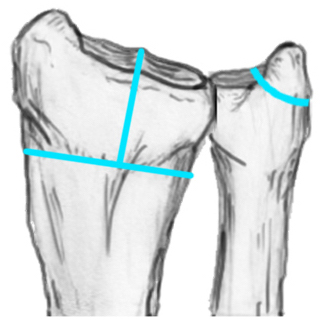

Radial angles

| Volar tilt mean 11° | Radial inclination mean 22° | Radius mean 11 mm longer than ulna |